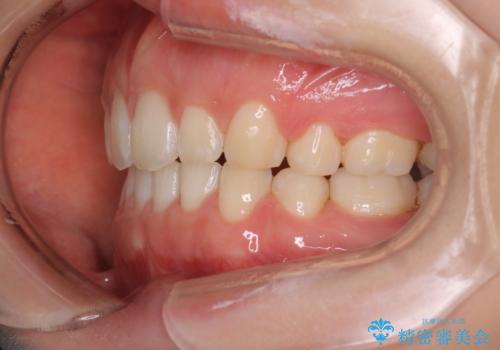

- 横から見たときの口元が出てるの気になるとのことで来院されました。

口元の突出感と口唇の閉じずらさが確認されました。

上下左右の歯を1本ずつ、合計4本抜歯しして前歯を後方に下げて、口元の突出感を改善する計画としました。

前歯をしっかり下げることで、口元がすっきりしました。